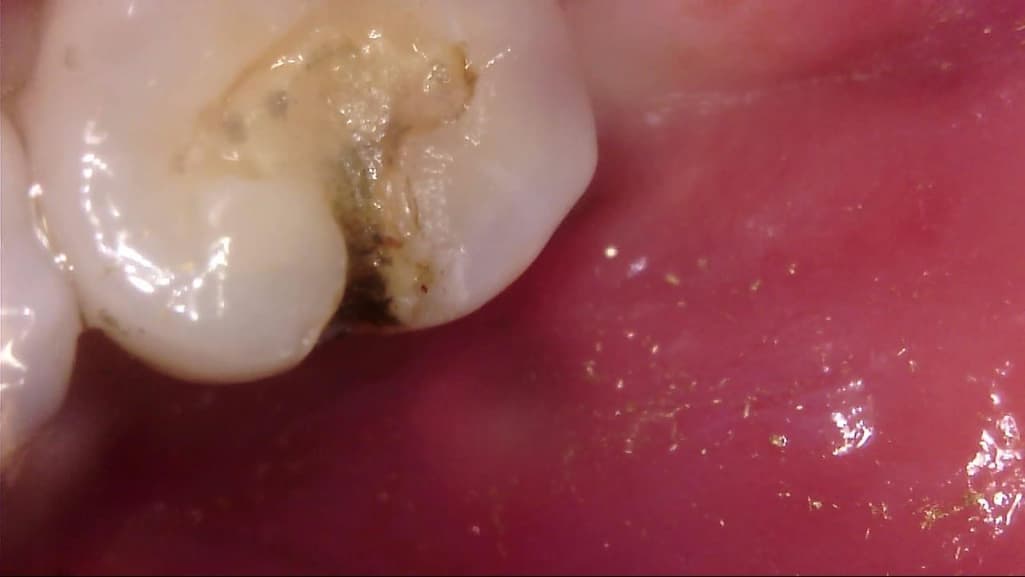

이차 우식이 상당히 깊게 발생하였는데, 치료 과정에서는 아래 사진과 같이 선생님께서 아래와 같이 일부 갈색 부분을 남긴 채 치아 삭제를 마치고 보철을 진행해 주셨습니다.

선생님께서는 "해당 부분은 착색 부위로, 이대로 덮어도 무방하다"라고 말씀 주셨고, 저 역시 더 이상 파고들어가면 신경치료가 예상되어 최선의 치료를 해 주셨다고 생각합니다.

다만 1) 해당 부위가 우식이 아닌 '착색'이 맞는지, 2) 해당 상태에서 보철물 안에서 추가 우식이 빠르게 진행될 가능성이 있는지, 3) 차라리 신경치료를 감수하고서라도 갈색 부분을 전부 없애는게 나았을지 불안감이 있는데, 관련하여 고견을 여쭙고 싶습니다.

사진에 보이는건 일단 착색과 2차 충치가 섞여 잇는거 같습니다. 충치를 제거하는 저스피드 기구로 제거를 해보기너 눌러 봐서 단단하면 충치가 아닙니다.

착색은 아니고 이환 상아질 남긴 것 같습니다 감염 상아질은 깔끔하게 다 제거 됐습니다

충치가 맞는 것으로 보이지만, 직접 기구를 가져다 대보지 않으면 확신을 할 수는 없습니다.